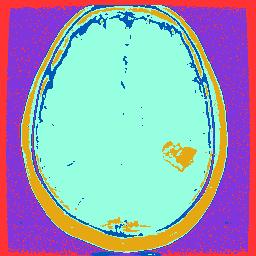

但是我得到的图像是:

我可以肯定地说,我的聚类管道是正确的,因为它符合书中的结果。

但我不确定星火是否在分类后对Dataframe上的字节顺序排序,可能会破坏结果。

我现在得到的结果是: